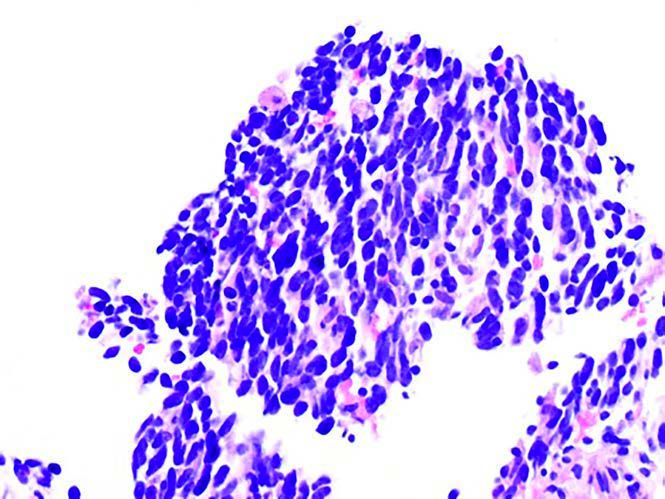

Figure 1 CT-guided needle biopsy, left upper lobe: small cell neuroendocrine carcinoma (H&E, 400X magnification).

A 70-year-old white woman with a 40 pack-year history of smoking has been on follow-up for previously detected abnormal lung nodules during the past 3 years. The most recent computed tomography (CT) scan revealed an increase in the size of the left upper lobe nodule-from 4 mm a year ago to 2 cm on the current CT scan. A CT-guided needle biopsy of this nodule revealed small cell lung carcinoma (Figures 1A and 1B). Further work-up with a positron emission tomography (PET) scan confirmed the left upper lobe lesion with a standard uptake value (SUV) of 12.7, and also revealed a right upper lobe nodule (1.1 cm in size) with an SUV of 2.1 (Figures 2A and 2B). Following multidisciplinary evaluation at the thoracic oncology tumor conference, the patient underwent initial bronchoscopy with ultrasound (endobronchial ultrasound [EBUS]) and biopsy of lymph node levels 10, 7, and 4, followed by a right-sided video-assisted thoracoscopic surgery (VATS) and a wedge resection of the right upper lobe nodule, and a left upper lobe lobectomy (Figure 3). Mediastinal lymph node dissection revealed no lymph node involvement. Pathology of the right upper lobe wedge resection revealed a 1.3-cm non–small cell lung adenocarcinoma, and pathology of the left upper lobe lobectomy revealed a 2.5-cm small cell lung carcinoma (Figures 4A and 4B). Both tumors had visceral pleural involvement and were resected with clear margins. The right upper lobe tumor was staged as pT2N0 and the left upper lobe tumor was staged as pT2N0 (per the 8th edition of the American Joint Committee on Cancer staging system).

In addition to identifying the morphological characteristics of subtypes of NSCLC and small cell neuroendocrine tumors, immunohistochemical staining for cytokeratin (5, 6, 7, and 20), p63, thyroid transcription factor-1, chromogranin, synaptophysin, and Ki-67 have been widely utilized as initial diagnostic tools. While the diagnosis of SMPLC with different histologies may be straightforward, distinguishing second primary lung cancer versus intrapulmonary metastasis in synchronous tumors of the same histology can be hard. The ability to determine the clonal origin of SMPLC may be essential in differentiating between the possibility of a single clonal event resulting in a tumor with subsequent spread into other parts of the lungs versus multiple independent tumors arising in an area due to a common carcinogen exposure or a genetic predisposition. To address this challenge, different molecular approaches have been explored. Currently, this is an area of ongoing research. In a series of 14 patients with synchronous NSCLC, Shimuzu et al reported a clonal relationship in 11 (79%) of cases by analyzing the loss of heterozygosity (LOH) and p53 mutations.14 Similarly, Wang et al documented a clonal relationship in 77% of 30 patients with multifocal lung tumors utilizing LOH, p53 mutations, and X chromosome inactivation status.15 More recently, Warth et al evidenced that at least 64% of patients with synchronous multiple primary NSCLC had a clonal relationship by utilizing a combined assessment of LOH (using a panel of 14 polymorphic microsatellite markers) and KRAS and endothelial growth factor receptor mutations.16 This is an area of burgeoning research and new discoveries are eagerly waited.